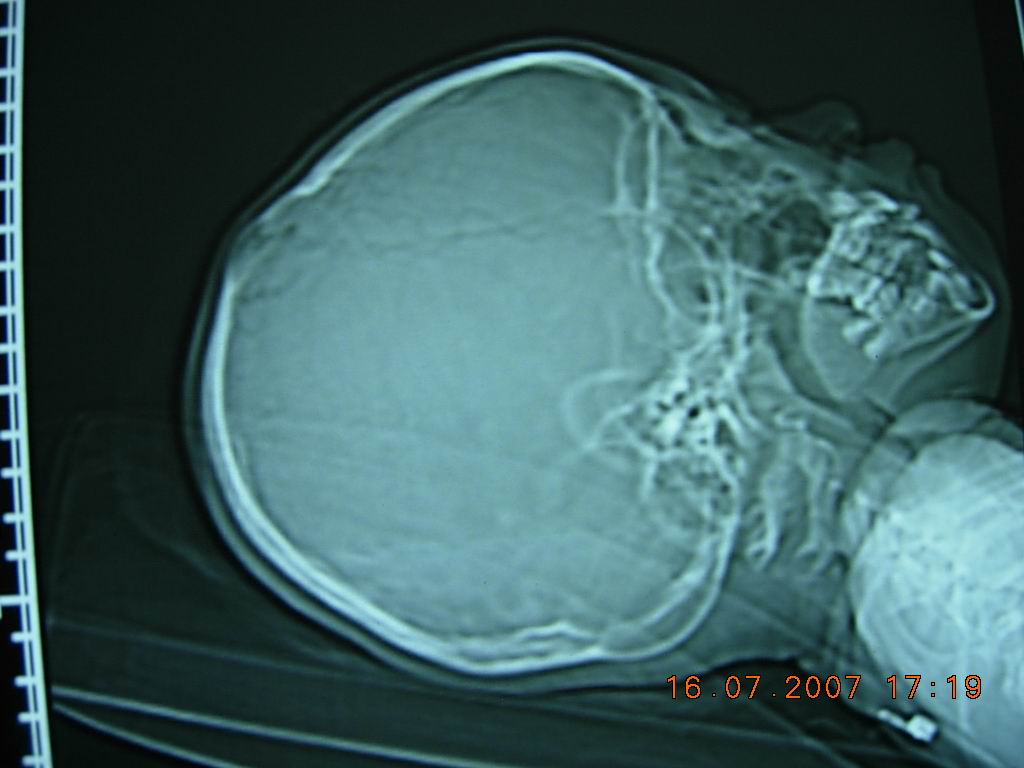

10岁女孩,家人十天前无意中发现顶部一硬的骨性突起,大小约3cm*4cm,无阳性临床症状。头颅ct如图所示。右顶骨内板骨质吸收消失,局部板障欠清,外板变薄呈局限性的轻度隆起,颅内脑实质未见异常征象。头皮软组织未见明显肿胀。考虑颅骨发育异常可能性大。请各位高人及同道指导,发表高见。

典型的顶骨大蛛网膜颗粒压迹。详见《中华放射学杂志》1994年第9期

chinese journal of radiology 起止页码:611-613国际标准刊号:issn 1005-1201国内统一刊号:cn 11-2149顶骨大蛛网膜颗粒迹:(附100例分析)

笔者分析100例顶骨大蛛网膜颗粒压迹,总发生率为19.8%,头颅正位片呈卵圆形或圆形骨质密度减低区,直径大于10mm,常位于顶前1/3区,对称分布于中线两侧、侧位或切线位呈弧形隆起,很象病理改变。

本例为右侧顶骨单发。

将上述杂志讨论部分简述如下:蛛网膜颗粒压迹大家已熟知,常位于中线两侧25-30mm 区内,直径2-4mm,圆或卵圆形骨质密度减低区,有的有引流静脉相连。

顶骨大于10mm的蛛网膜颗粒压迹,尚无专题报道,在临床实践中,常被误诊为病理改变,熟悉其特点,有利于鉴别诊断,避免不必要的检查。根据本组分析,特点如下;1、大的蛛网膜颗粒压迹以20岁以前多见,常因偶尔发现顶骨局限性隆起而就诊。2、头颅正位片呈卵圆形或圆形骨质密度减低区,对称分布于中线两侧,边缘清楚,上半部较硬,双侧大小各异。3、侧位片成弧形隆起,颅板变薄,重者内外板及板障分界不清,仅呈一致密弧线。4、弧形隆起常在冠状缝后方,极少跨越冠状缝。5、隆起的头皮组织正常。6、临近可见小蛛网膜颗粒压迹,但无异常血管沟。

正位片骨质密度减低,似颅骨病变,但切线位和侧位呈典型的颅板内压性改变,不同于颅骨嗜酸性肉芽肿,皮样或表皮样囊肿等病变所致的颅骨缺损,后者病变来源于板障,切线位片颅骨内外板分别向内外膨隆或翘起。脑凸面胶质瘤,脑外蛛网膜囊肿或硬膜内或外慢性血肿或水瘤都可压迫或侵蚀颅板,使其变薄,隆起或缺损,但大的蛛网膜颗粒压迹的部位和双侧对称分布,不同于前者。先天性顶孔很像顶骨大蛛网膜颗粒压迹,但前者是先天异常,位于顶后1/3区,双侧对称,大小各异,直径偶达数厘米,有导静脉通过,可触及骨缺损和波动。正位片呈圆或卵圆形缺损区,边缘锐利,无硬化,侧位或切线位呈局部颅板缺损,不是弧形隆起。

分析:本例侧位定位像表现典型,ct显示右侧改变,与报道者双侧多对称不同,但上述其他病变均可排除,诊断还是成立的。敬佩解放军总医院陈巨坤等对此征象的研究,到其发表时尚无专题报道。我94年就拜读此文,并应用于实践,注意观察,此征确实不少见。我认为应该属于正常变异。(发生率20%左右)